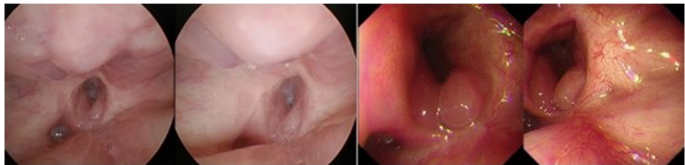

本刊推荐:为解决下咽癌侵犯颈段食管术后缺损修复难题,浙江大学团队开展喉气管瓣(LTF)重建技术研究。研究证实LTF可有效修复缺损(5年总生存率42.9%),并创新采用低温等离子消融术联合导尿管扩张术成功解决术后咽食管狭窄(PES)问题,为晚期下咽癌患者提供了创伤小、可行性高的重建方案。